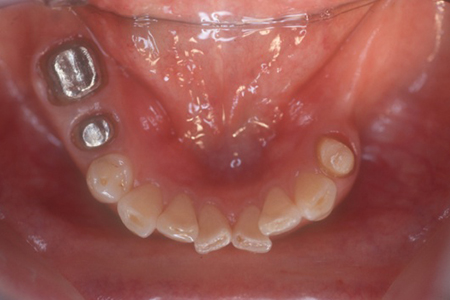

上下顎の症例 矯正して動揺歯を固定

治療期間 3年 費用 600万(税別)

インプラントが10本埋入されました

術後12年

現在メインテナンス中で経過良好です

リスク・副作用としてインプラント周囲炎があります